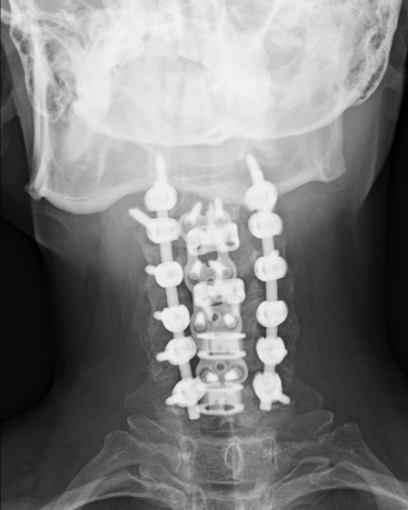

So imagine my surprise when a few months shy of my 10 year anniversary (traditionally tin or aluminum, but I think titanium is more appropriate), I had a “minor event”, and the follow-up appointment revealed I needed a second surgery, which would be more complicated than the first and the only available day for the rest of the year was my birthday.

- I think my x-rays are really cool and wanted to share them!

I hope you’ve enjoyed this little tour of my spine (cross your fingers this is the last intervention!) and as always, if I can be of service to you, please do not hesitate to reach out to schedule a Complimentary Design Discovery Consultation.